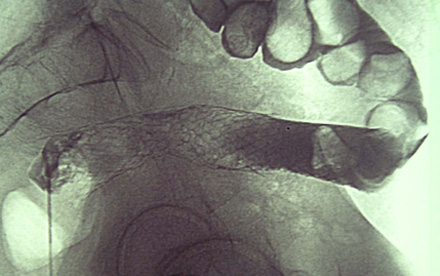

Radiologist passing stent.

Plain film showing stent in situ.

The principles behind stenting are:

- Place a stent through the stenotic area by radiologist/endoscopist